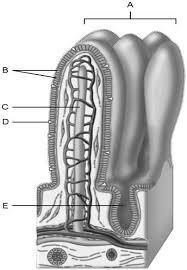

Mucosa

A

Duodenal glands found here

B

Smooth muscle layer.

C

Serosa.

D

Area of the lamina propria

A

Continuation of the mesentery

D

Absorptive cells that line the intestinal tract

B

Cell type specialized to secrete mucus into the lumen of the intestinal tract.

D

Wide lymph capillary located in the villus.

C

Paneth cells are found here.

E